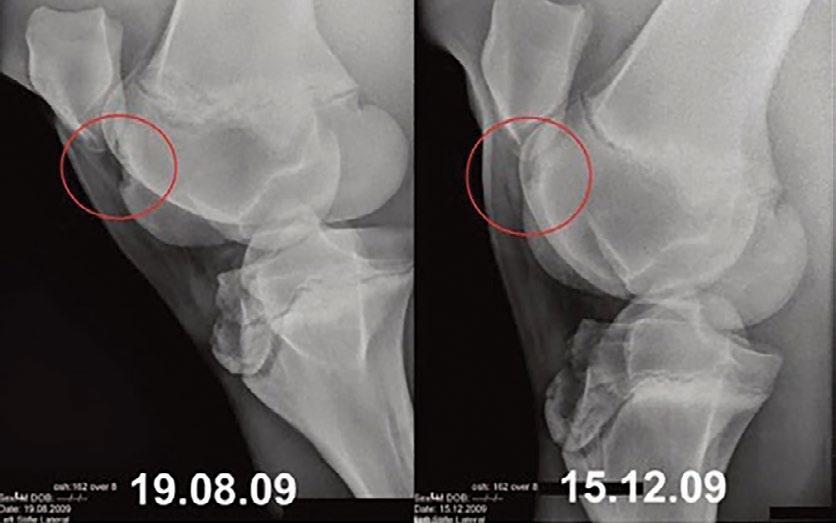

A Bientot (as the French say), Publisher and Editor-in-Chief Sarah Appel in Paris with her daughters Ella (left) and Piper (right)Did you know horses without access to fresh pasture can lose bone density in just 7-10 days?

Vitamins K1 and K2 found in fresh green grass are critical to the function of osteocalcin which supports bone density and healthy bone formation.

Horses with limited access to high quality pasture are likely deficient in vitamin K which can result in a loss of bone density and increase the risk for bone related disorders and injury.

BONAFIDE® contains the patented active ingredient Quinaquanone®, a water-soluble and bioavailable form of vitamin K1 and K2 which improves overall bone density and strength.